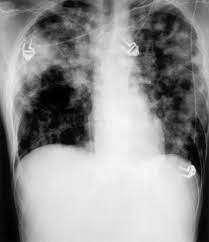

While some infections are subclinical, others result in localized acute or chronic disease, or fatal septicemia. Melioidosis infectionscan present like an infected wound, with swelling or ulcers at the exposure site, but they can also occur in the lungs, the bloodstream or widely spread throughout the body. Melioidosis is an often fatal infectious disease caused by the environmental bacterium, burkholderia pseudomallei.melioidosis is often misdiagnosed because it causes wide range of symptoms which often mimic those of other tropical diseases. It stems from bacteria found in contaminated water and. Melioidosis is an infectious disease caused by the bacteria burkholderia pseudomallei which is found in contaminated water and soil. An accurate map defining the global distribution of b. Because it can affect almost any organ, melioidosis can mimic many other diseases; Melioidosis, also known as whitmore's disease, is a bacterial infection that can affect both people and animals. Melioidosis is predominantly a disease of tropical climates and is spread to humans and animals through direct contact with the contaminated source. Melioidosis infection commonly involves the lungs. What are the symptoms of melioidosis? Melioidosis is a disease caused by bacteria called burkholderia pseudomallei. Melioidosis treatment usually starts with an iv antimicrobial infusion that lasts for a minimum of two weeks, the cdc says.

Pseudomallei from any clinical specimen is considered diagnostic for melioidosis. It is predominately a disease of tropical climates, especially in southeast asia and northern australia where it is widespread. Because it can affect almost any organ, melioidosis can mimic many other diseases; What are the symptoms of melioidosis? The disease occurs mostly in tropical areas of the world, primarily southeast asia and northern parts of australia. Melioidosis infection commonly involves the lungs. Melioidosis is potentially preventable, but there is a striking lack of evidence on which to base an effective prevention programme. Melioidosis is a bacterial disease that affects humans and many species of animals.